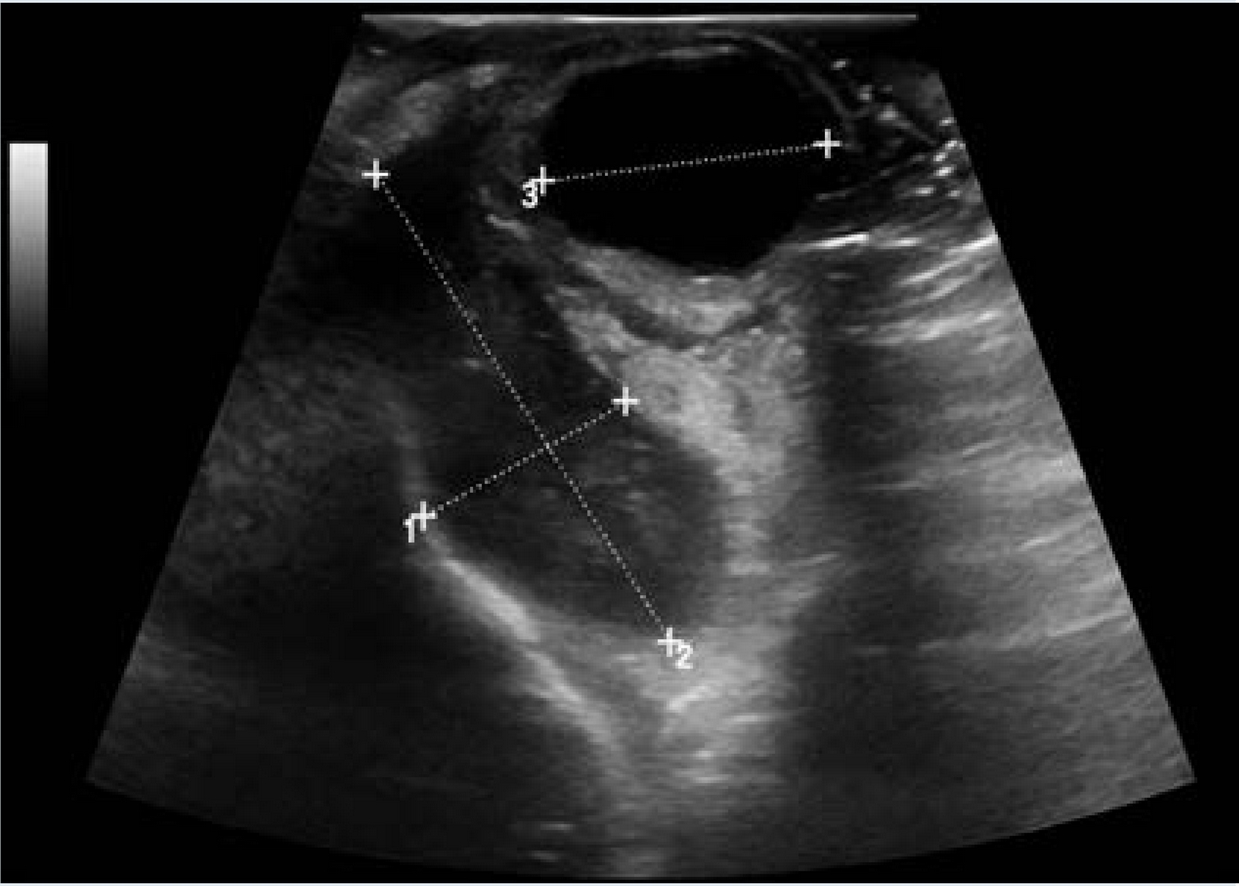

La ultrasonografía ocular reportó una lesión heterogénea que ejercía compresión y desplazamiento en sentido anterior del globo ocular derecho, y datos de inflamación de tejidos blandos (Figura 1). La tomografía computada describió la lesión como heterogénea e identificó datos de sinusitis y proptosis (Figura 2). Por resonancia magnética se reportó la misma lesión con aspecto heterogéneo de 5.5 ' 2.5 cm en sus diámetros mayores, que involucró tejidos musculares y con efecto de masa sobre estructuras orbitarias. No se observó extensión intracraneal, a cavidades paranasales ni al seno cavernoso (Figura 3). Ante una proptosis de rápida evolución y sospecha de probable rabdomiosarcoma se realizó biopsia transconjuntival de lesión intraconal y tejido peri-orbitario. Las preparaciones histológicas de la lesión intraconal y de la grasa orbitaria mostraron tejidos blandos con un proceso inflamatorio, necrótico con vasculitis de vasos de pequeño calibre con afección ocasional a vasos arteriales y venosos de mayor calibre. La vasculitis fue a expensas de linfocitos e histiocitos con trombosis aislada y algunos granulomas mal constituidos. El proceso inflamatorio estaba constituido por linfocitos, histiocitos, células plasmáticas y en una zona se mezclan con numerosos neutrófilos con cariorexis; la necrosis fue isquémica. Se realizaron diversas tinciones de histoquímica convencional e inmunohistoquímica para descartar neoplasia linfoide maligna o proceso infeccioso granulomatoso como micobacterias u hongos. La glándula lagrimal mostró afección por el proceso inflamatorio, la necrosis isquémica y la propia vasculitis. El diagnóstico fue de: granulomatosis de Wegener (Figura 4).

Figura 1 Ultrasonido ocular. Se observa compresión y desplazamiento en sentido anterior del globo ocular derecho, incremento del grosor del músculo recto externo con incremento de su vascularidad, con compresión y desplazamiento lateral y medial sobre la región del cono. Al rededor del músculo se observó un halo ecogénico considerado como celulitis con involucro de tejido adiposo, correlacionado con aumento de volumen del tejido celular subcutáneo del párpado inferior de aspecto heterogéneo.